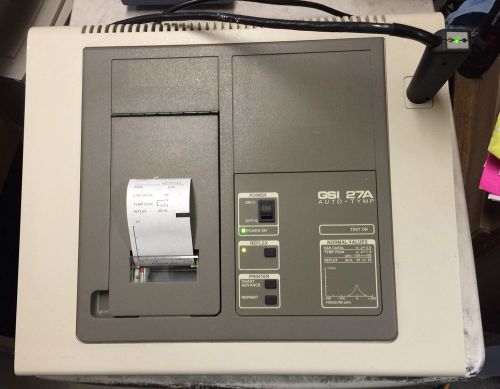

Grason Stadler GSI 27A Auto Tymp Tympanometer